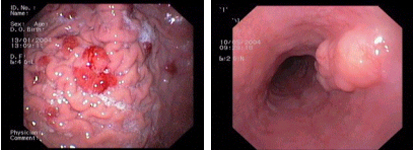

Endoscopic images:

imagen2

Kaposi's sarcoma in the stomach - Submucosal tumour of the oesophagus